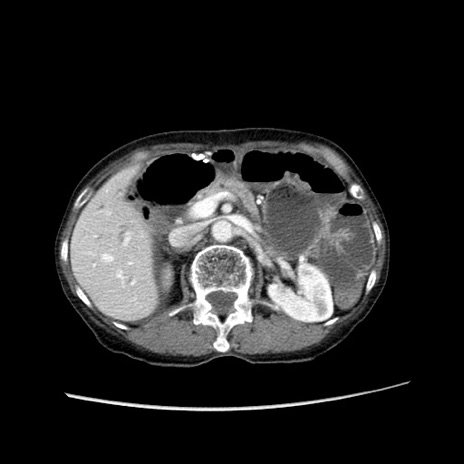

症例25(横断像)

【症例】80歳代女性

【主訴】胸のつかえ感

【現病歴】約9時間前に食後から胸のつかえた感じあり、嘔吐あり、来院。

【既往歴】胃癌(全摘)、胆摘、虫垂炎

【身体所見】心窩部に圧痛あり、反跳痛なし。

【データ】WBC 5700、CRP 0.05